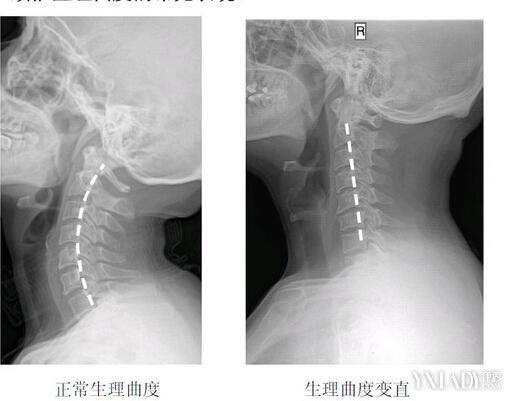

看了最近拍的頸部x光片明顯發現頸椎過直⋯⋯⋯⋯(X光影片在下方留言影片中),正常的頸椎是有類似C字型的弧線,這是最好的頸椎曲線代表中醫所說的「骨正筋柔」,頸椎的椎間盤可以說是人體天然的避震系統,在有頸椎前凸C字型弧形的保護作用下,頸椎的小關節面承受的壓力是最小的!當然可以撐到六七十歲以上,但是!!!一但頸椎生理曲線消失,關節面的壓力會急遽增加,頸椎周邊的肌肉包括頭後大小直肌、頸夾肌、頭夾肌、提肩胛肌也會因為曲線的消失,形成許多高應力點